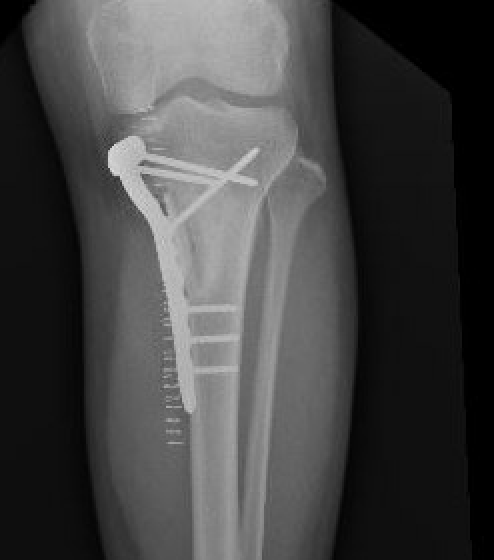

Management

Intra-lesional curettage & bone grafting / cement

Recurrence common (25%)

Treat recurrence with wide resection